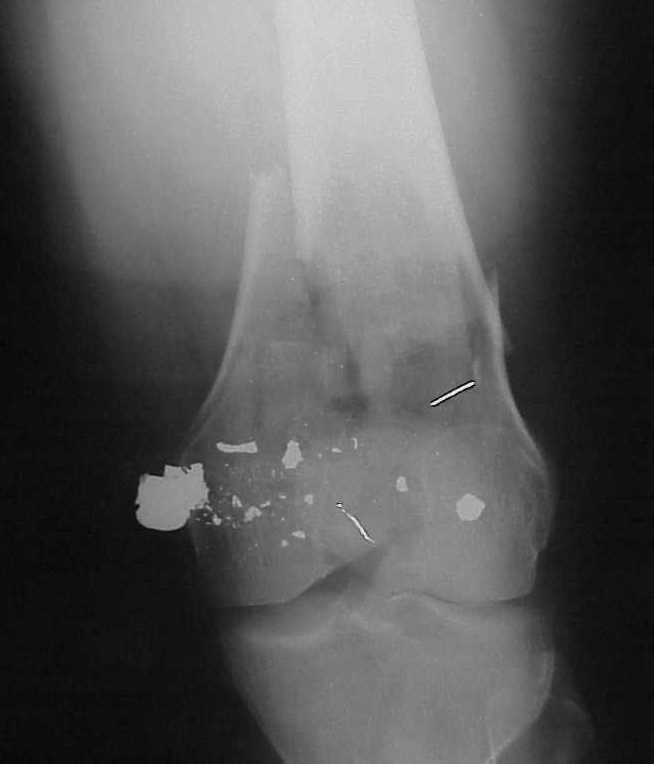

A CT and knee xrays would help identify lateral condyle comminution and/or a "hoffa fragment" of the posterior condyle. I am concerned that the lateral cortex is not sufficient to give purchase for a retrograde IMN. blocking screws could improve this as a possibility. A long blade or LISS if avaible would be my secondary choices. Good luck. Any chance you can get these cases transferred earlier when it

Lateral condyle looks too small for the blade, and the plate too short.

I am sure that you assessed adequately the condylar fractures, they may need fixation (eg. percutaneous screws).

Насчет стабильности для ранней нагрузки, конечно, сомнительно, но при таком повреждении ранняя нагрузка противопоказана в любом случае. Для ранних движений Должно хватить. Снимки в следующем сообщении.

воспользовались для репозиции, см. приложение.